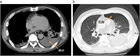

1. 食道破裂(esophageal rupture)、食道穿孔(esophageal perforation)や食道断裂(esophageal disruption)とは、食道壁に全層性に断裂(disruption)や損傷(trauma、injury)が生じた状態である。

1. 胸痛、呼吸困難、ショックなどの症状を呈する。